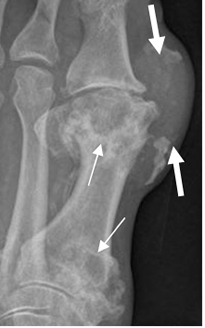

Fig 33. Artropatía por gota.

Rx AP del pie. Lesiones radiolúcidas y de bordes escleróticos, en el 1º metatarsiano. Hay prominencia asociada de los tejidos blandos, que corresponde a tofo. (Flecha gruesa).